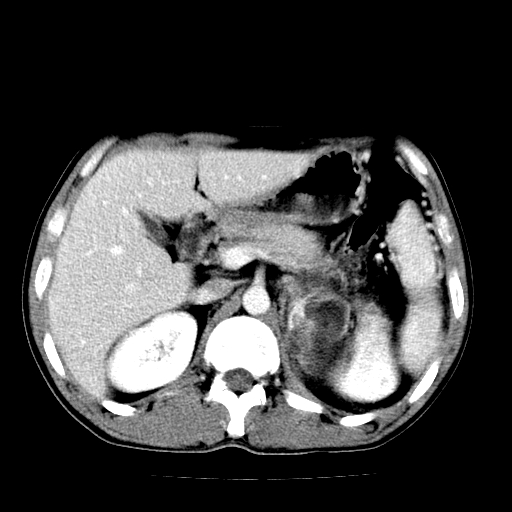

以下是引用天南地北在2007-4-30 13:36:00的发言:[br]支持慢性胰腺炎伴有假性囊肿

以下是引用andymaomao在2007-4-30 14:28:00的发言:[br]支持:1.慢性胰腺炎并假性囊肿形成可能;[br] 2.左肾形态稍增大,旋转不良。